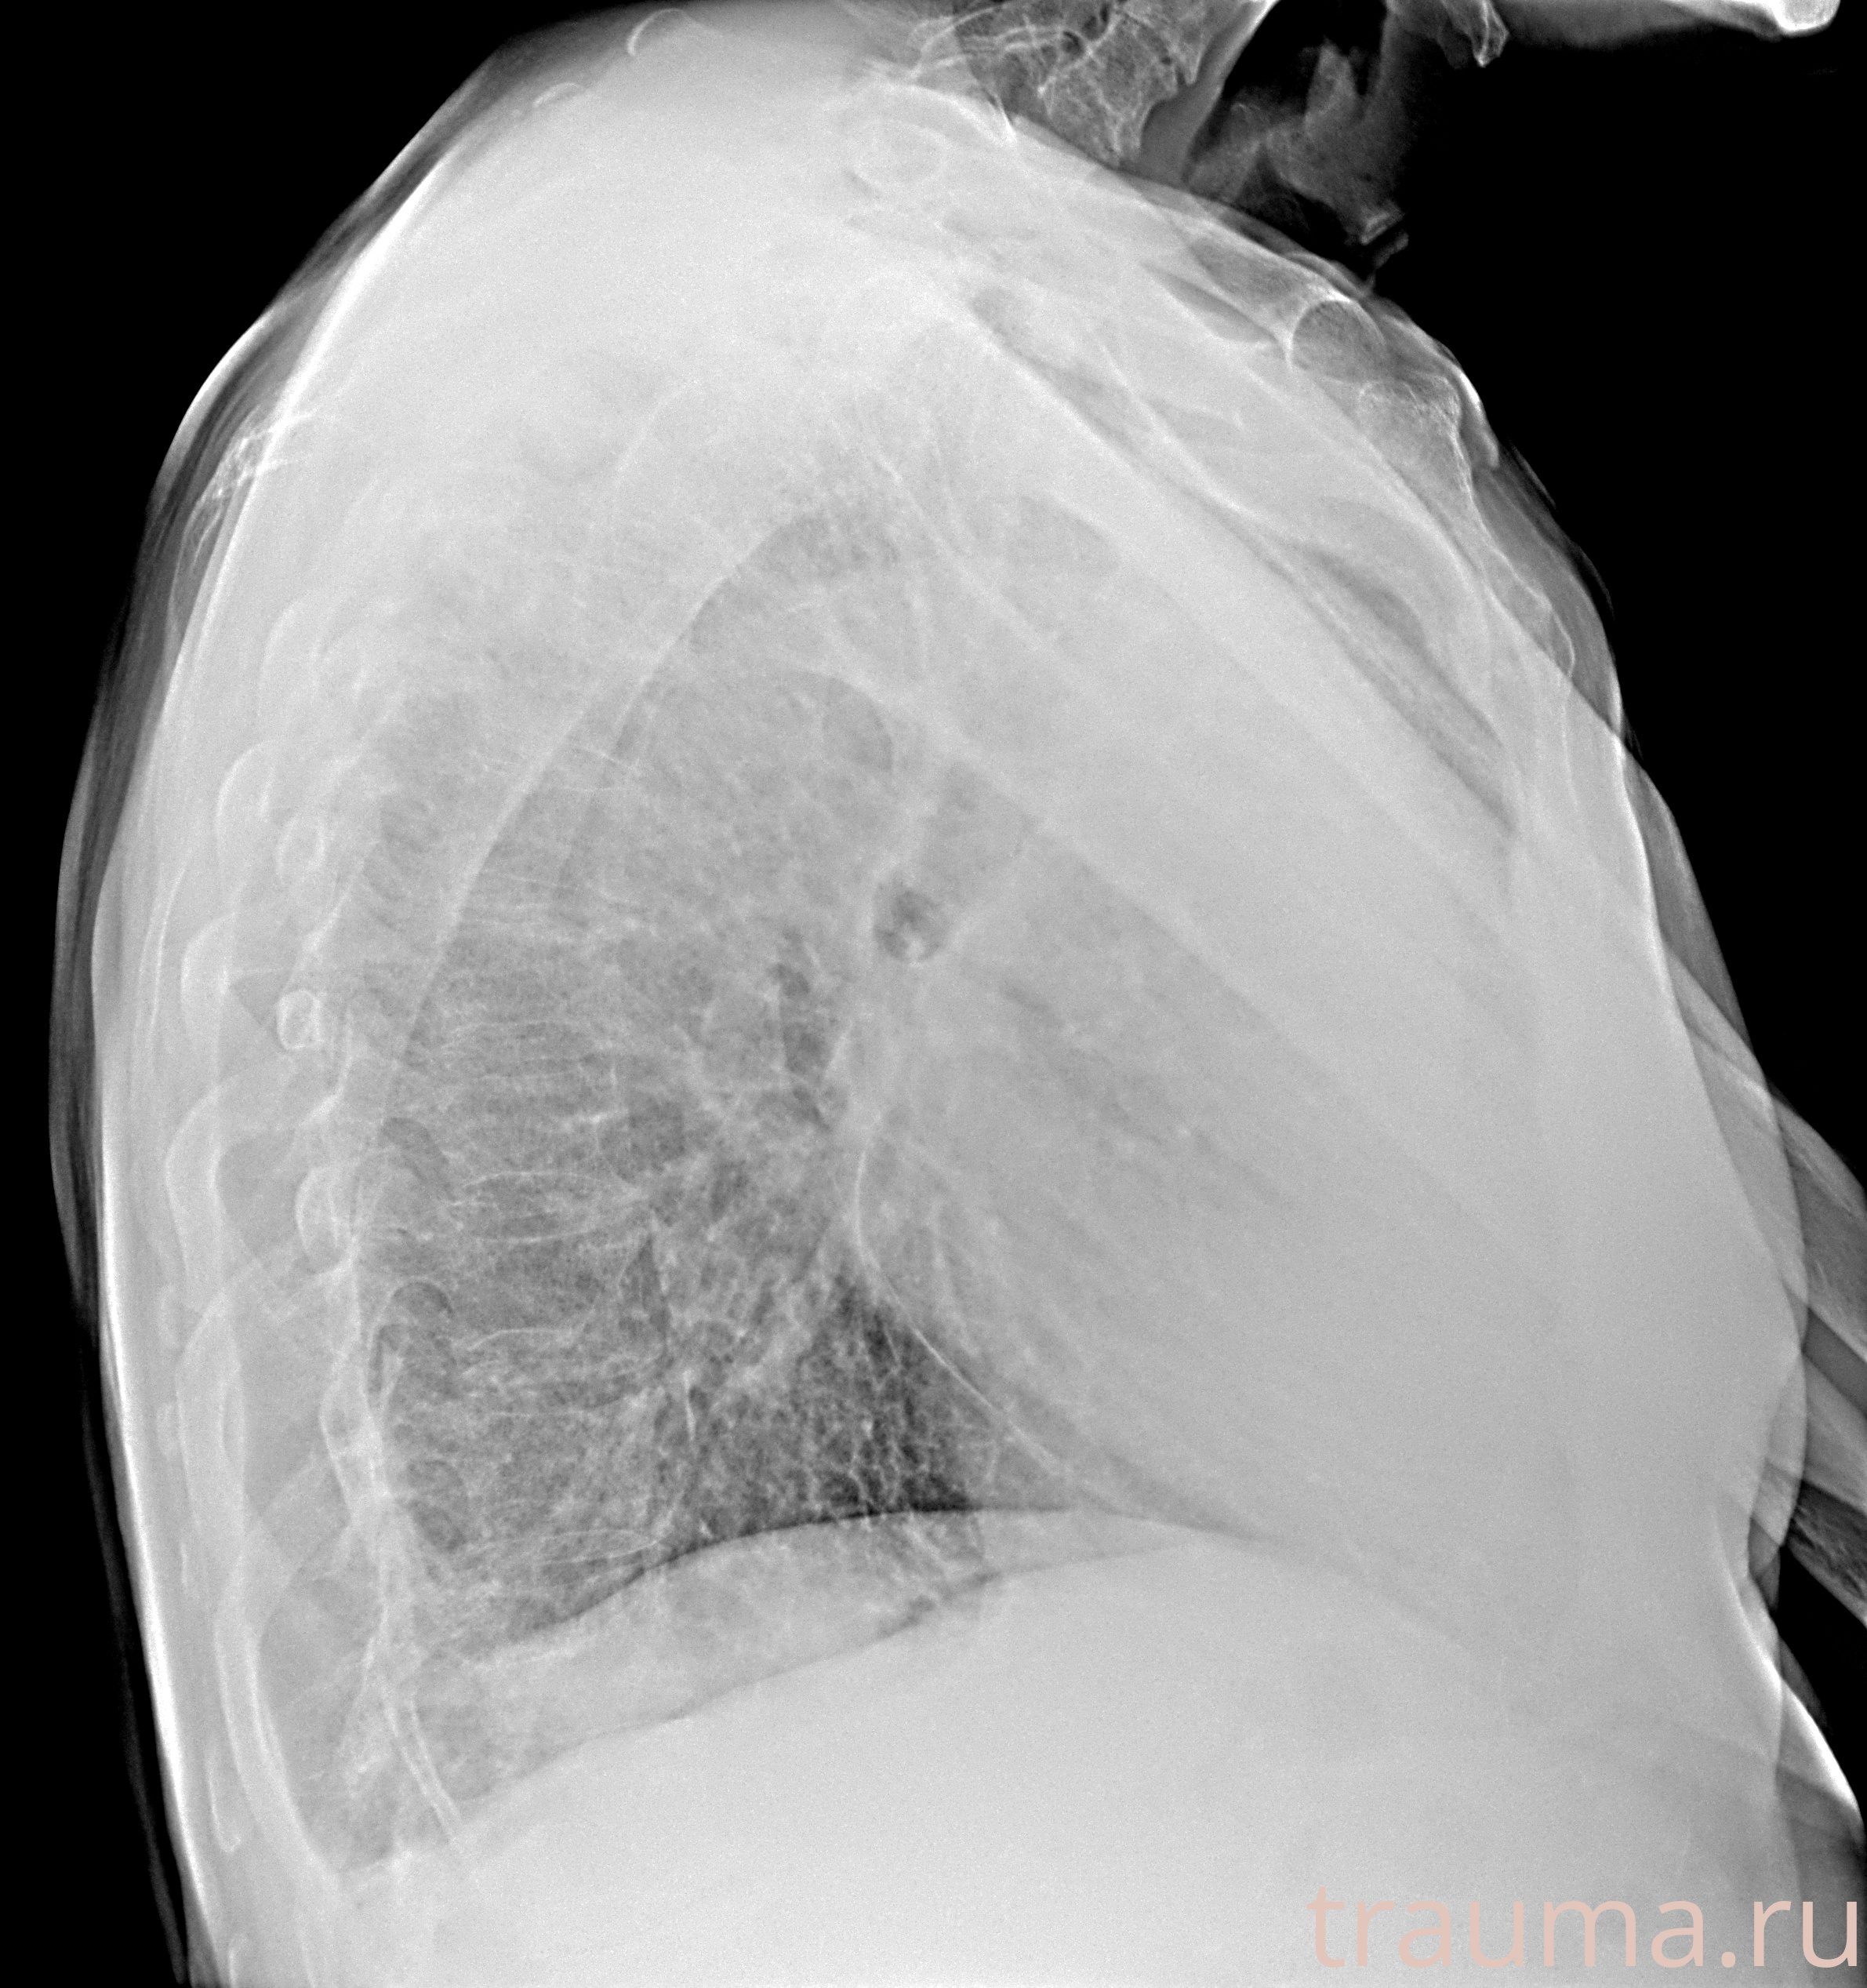

Рентгенограммы

Рентген на дому: по вашему адресу приезжает врач-рентгенолог, травматолог-ортопед с мобильным рентгеновским аппаратом, проводит диагностику травмы или заболевания, делает необходимые рентгенограммы, дает рекомендации по дальнейшему лечению. Получить качественные снимки в домашних условиях возможно благодаря уникальной методике, разработанной МосРентген Центром для института  Склифосовского